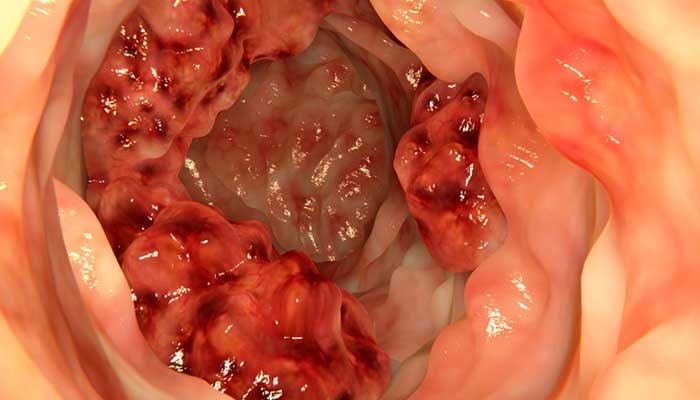

3️⃣ مناظير الجهاز الهضمي

✳️ المنظار العلوي للجهاز الهضمي ويطلب اذا كان المريض يعاني من اعراض قد تدل على اصابة المعدة او الاثني عشر

✳️ المنظار السفلي للجهاز الهضمي او ما يعرف بمنظار القولون

ويعتبر أدق الفحوصات لتمكين الطبيب من معاينة الامعاء بشكل مباشر مع اخذ الخزعات وارسالها للفحص المجهري في المختبر